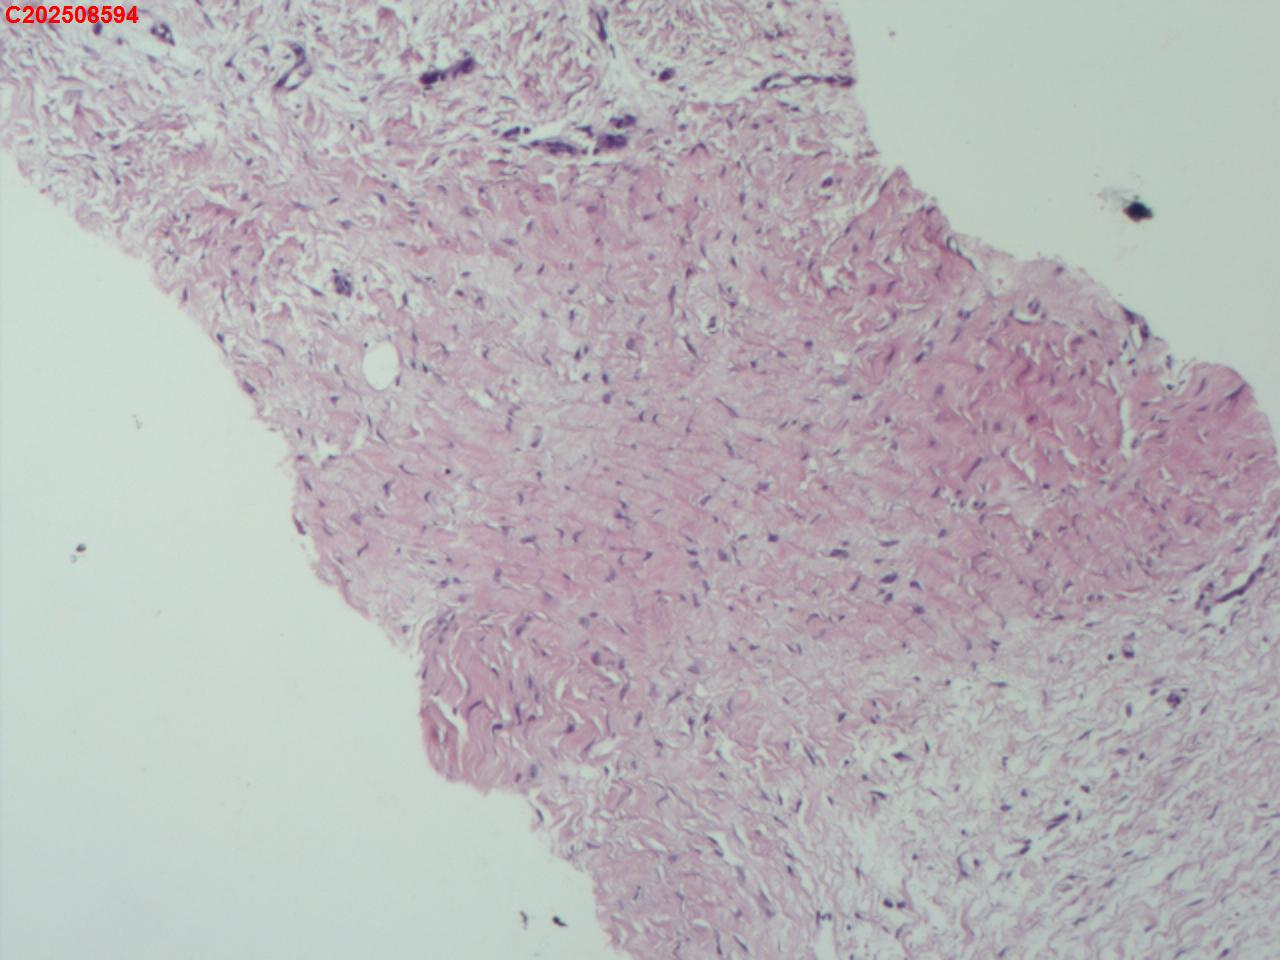

腰椎椎旁穿刺组织

性别年龄50岁临床诊断腰椎椎旁脓肿性质待查?

一般病史腰椎椎旁脓肿性质待查?

标本名称腰椎椎旁穿刺组织

大体所见腰椎椎旁穿刺组织2条

患者缘于入院前3个月无明显诱因出现腰腹痛,起初为隐痛,间断对症治疗,症状进行性加重,故入院前20天于某市第五医院就诊,查腰椎X片提示腰椎骨质增生,给予布洛芬、双氯芬酸钠等对症治疗,症状仍进行性加重,疼痛级别为5级,休息不能缓解,故入院前5天于某市第一人民医院就诊,查腰椎CT提示腰椎间盘膨出,腰椎退行性变,双侧腰大肌及背侧肌群增粗模糊致左侧输尿管下段粘连,尚短输尿管及肾盂扩张积水,腰背部皮下积液,嘱其回当地医院治疗,故入院前2天于某县中医院查彩超提示左侧腹腔内低回声包块,双肾积水、双侧输尿管上段扩张,右肾多发结石,遂于某市第二医院住院治疗,住院期间查CT提示双侧腰大肌及髂腰肌增厚、肿胀,左肾及输尿管腹段积水改变,腹膜后及左侧腹股沟区稍大淋巴结,左肺上叶及右肺中叶条索,胆囊多发结石子宫切除术后改变;血糖、肝肾功能、血脂基本正常,考虑腹腔结核可能。